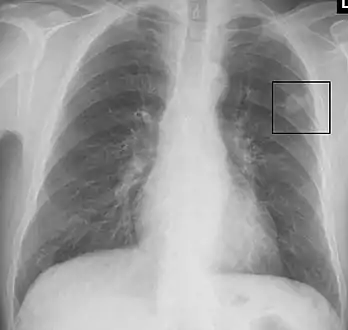

![]() | |

A coronal CT scan showing a malignant mesothelioma Legend: → tumor ←, ✱ central pleural effusion, 1 & 3 lungs, 2 spine, 4 ribs, 5 aorta, 6 spleen, 7 & 8 kidneys, 9 liver | |